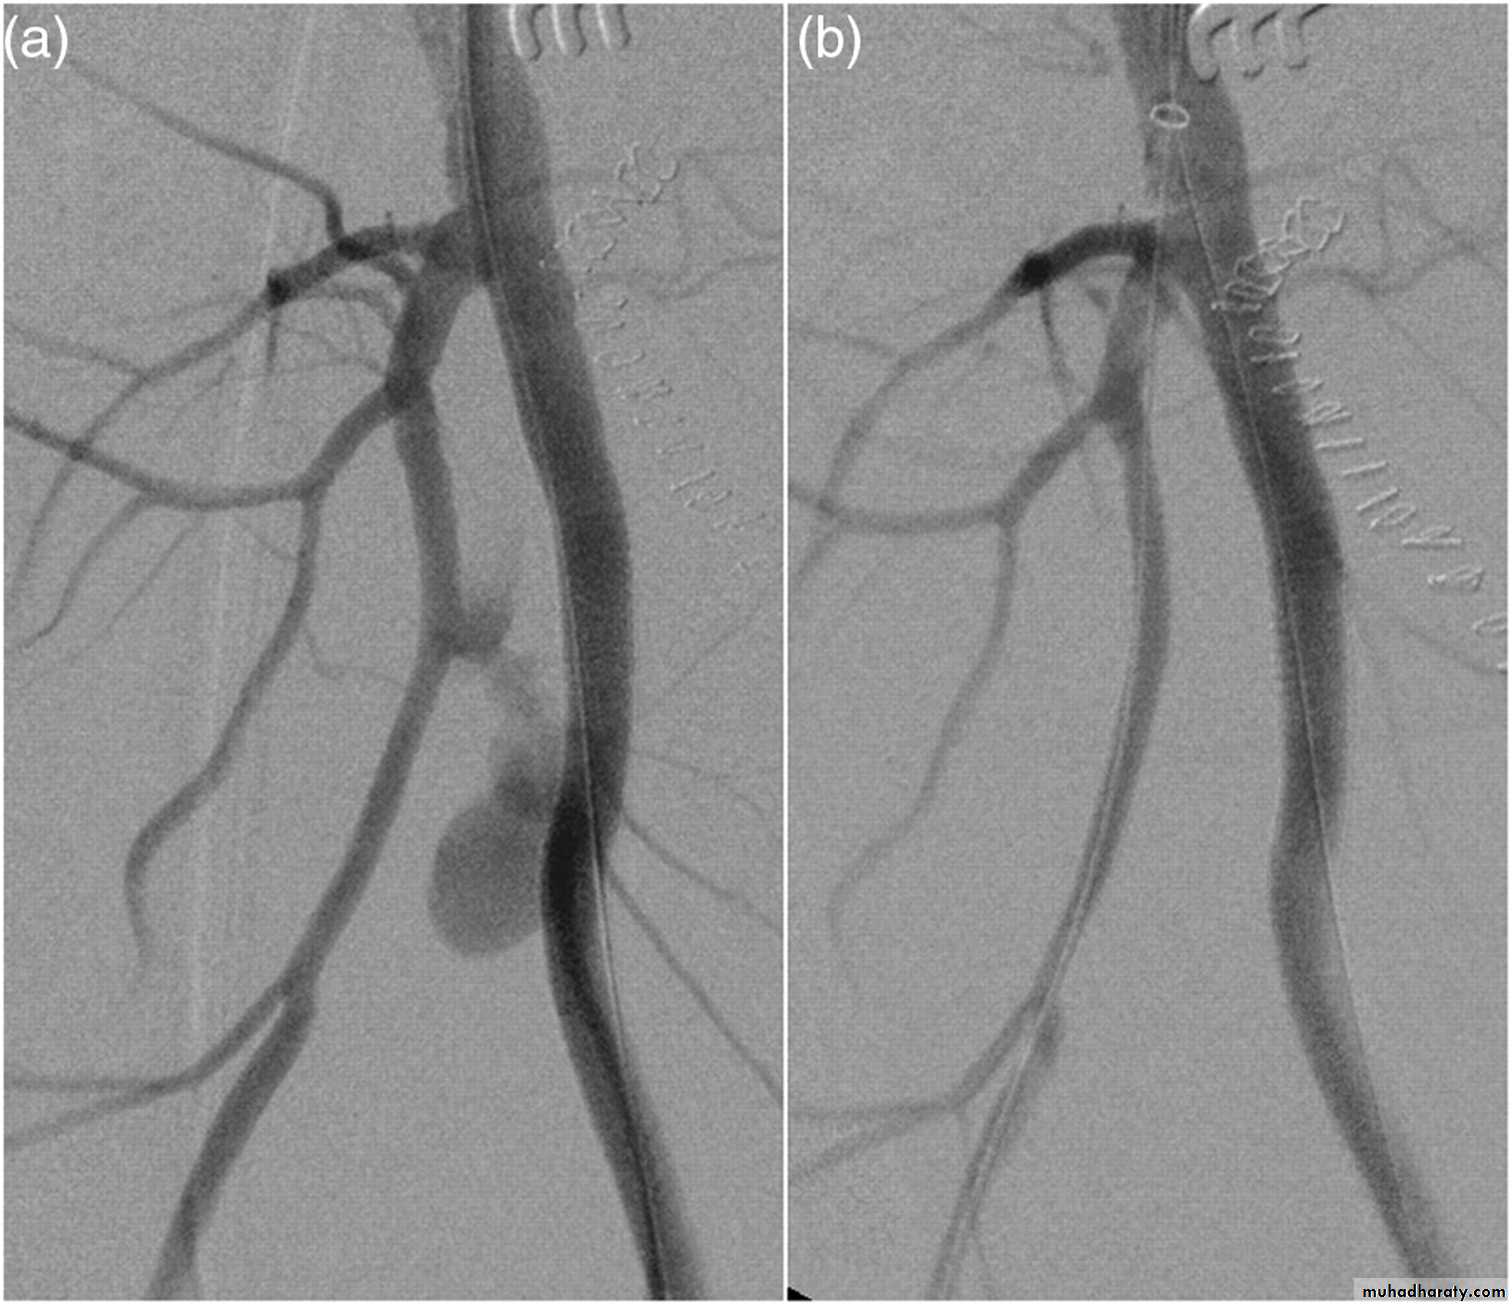

• Angiography

Angiography:

• Endovascular aneurysm repair